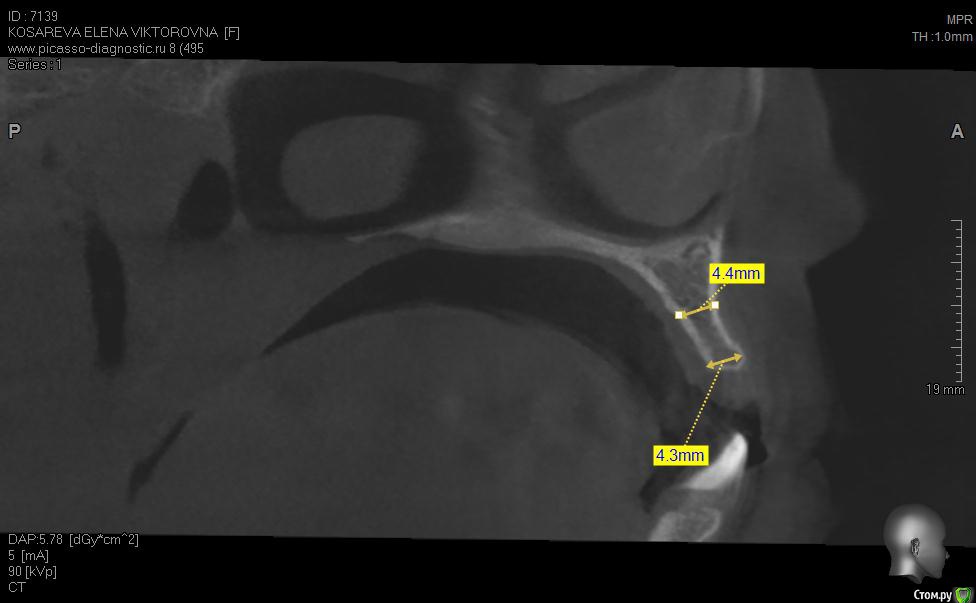

Уважаемые коллеги помогите пож с планом лечения, хотелось бы услышать ваши планы лечения,

пациент хочет красивую улыбку и импланты, клыки трогать категорически отказалась как опоры под временные на период интеграции имплантов